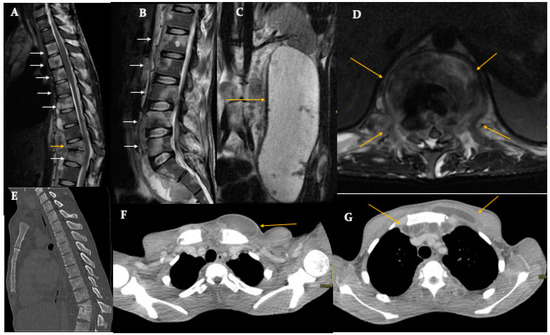

AMIRSYS Diagnostic Imaging Spine 2004 RossBrant-Zawadzki・Moore 043LaD Diagnostic Imaging: Spine - 4th Edition | Elsevier Shopの詳細情報

Diagnostic Imaging: Spine - 4th Edition | Elsevier Shop。Buy DIAGNOSTIC IMAGING: SPINE: 4TH EDITION Book Online at。Spondylodiscitis and Its Mimickers: A Pictorial Review。

Spondylodiscitis and Its Mimickers: A Pictorial Review

■商品名■

AMIRSYSDiagnosticImagingSpine2004RossBrant-Zawadzki・Moore

■出版社■

AMIRSYS

■著者■

RossBrant-Zawadzki・Moore

■発行年■

2004

■教科■

医学一般洋書

■書き込み■

見た限りありません。予めご了承お願い致します。付属品のプリントは実際に使用されたものであり、書き込みがある場合もございます。

■状態・その他■

この商品はCランクです。脳波判読step by step 症例編/大熊輝雄,松岡洋夫,上埜高志【著】。THE内科専門医問題集 WEB版付 1 Ver.2/医学書院/筒泉貴彦(単行本)。

Spondylodiscitis and Its Mimickers: A Pictorial Review